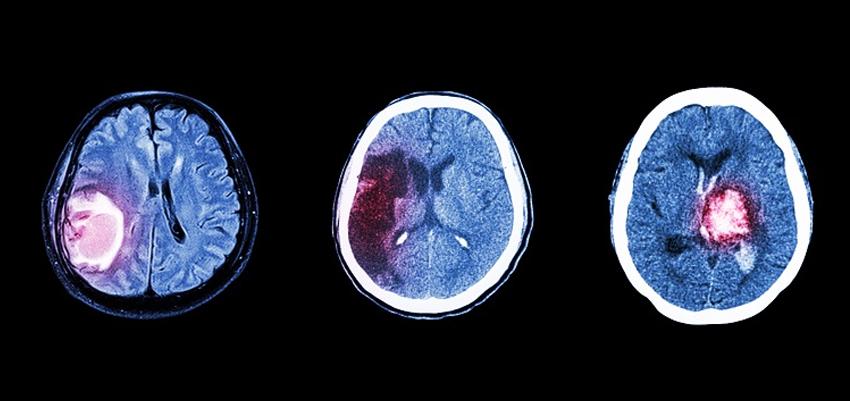

In the realm of medical advancements, the journey towards finding a cure for brain cancer has been both challenging and inspiring. As technology and research continue to evolve, so does the approach to patient care. Today, we delve into the concept of patient centric care and explore some of the finest brain cancer treatment centers that are at the forefront of this innovative approach.

Patient centric care is a healthcare approach that prioritizes the individual needs, preferences, and values of patients. In the context of brain cancer treatment, this approach is particularly crucial. Dealing with such a complex and life-altering condition requires not only cutting-edge medical interventions but also a holistic understanding of the patient’s emotional and psychological well-being.